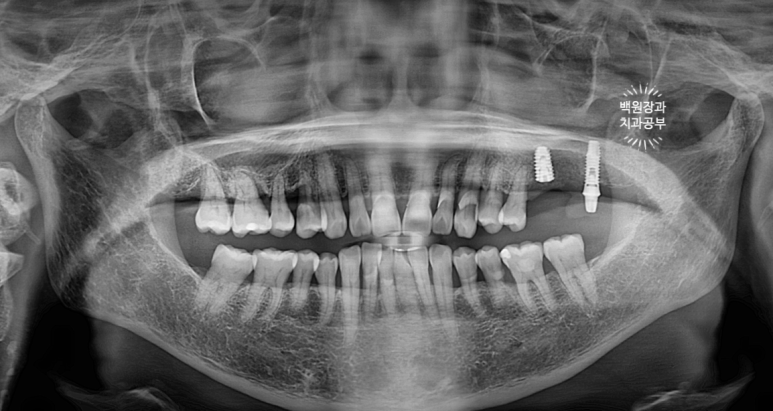

왼쪽 위 어금니를 치료받은지 2년 정도 되었는데,

자기 치아에 염증이 생겨서 빼야한다고 들었어요.

작년 말 저희 병원에 내원하셨던 중년 여성 환자분입니다.

왼쪽 위 어금니에 염증이 있어서 빼야한다고 들으셨다는데...

왠걸! 이런 보철물을 내가 직접 보게 되다니~

하나는 자연치아, 하나는 임플란트가 한 개의 보철물로 연결되어 있더라구요.

정확히 브릿지 (bridge)라고 부르지는 않지만, splinted crown 이라고 부릅니다.

교수님들 말씀이 맞았네요... 결국 자기 치아가 완전히 고장나버렸고,

주변은 염증이 가득 형성되서 잇몸뼈가 모두 사라져 버렸습니다.

처음 오셨을 때 입 안 사진으로 보면, PFM 크라운 두 개가 붙어있는 형태.

즉, splinted PFM crown 형태로 제작이 되어 있었어요.

추측컨데... 수술했던 임플란트 크라운이 너무 짧으니 잘 떨어질까봐 앞에 치아와 연결한게 아닐까 싶었습니다.

여튼.. 상부 보철물을 갈아서 뜯어내니, 여지없이 자연치는 쑥 빠져버렸습니다. ㅠㅠ